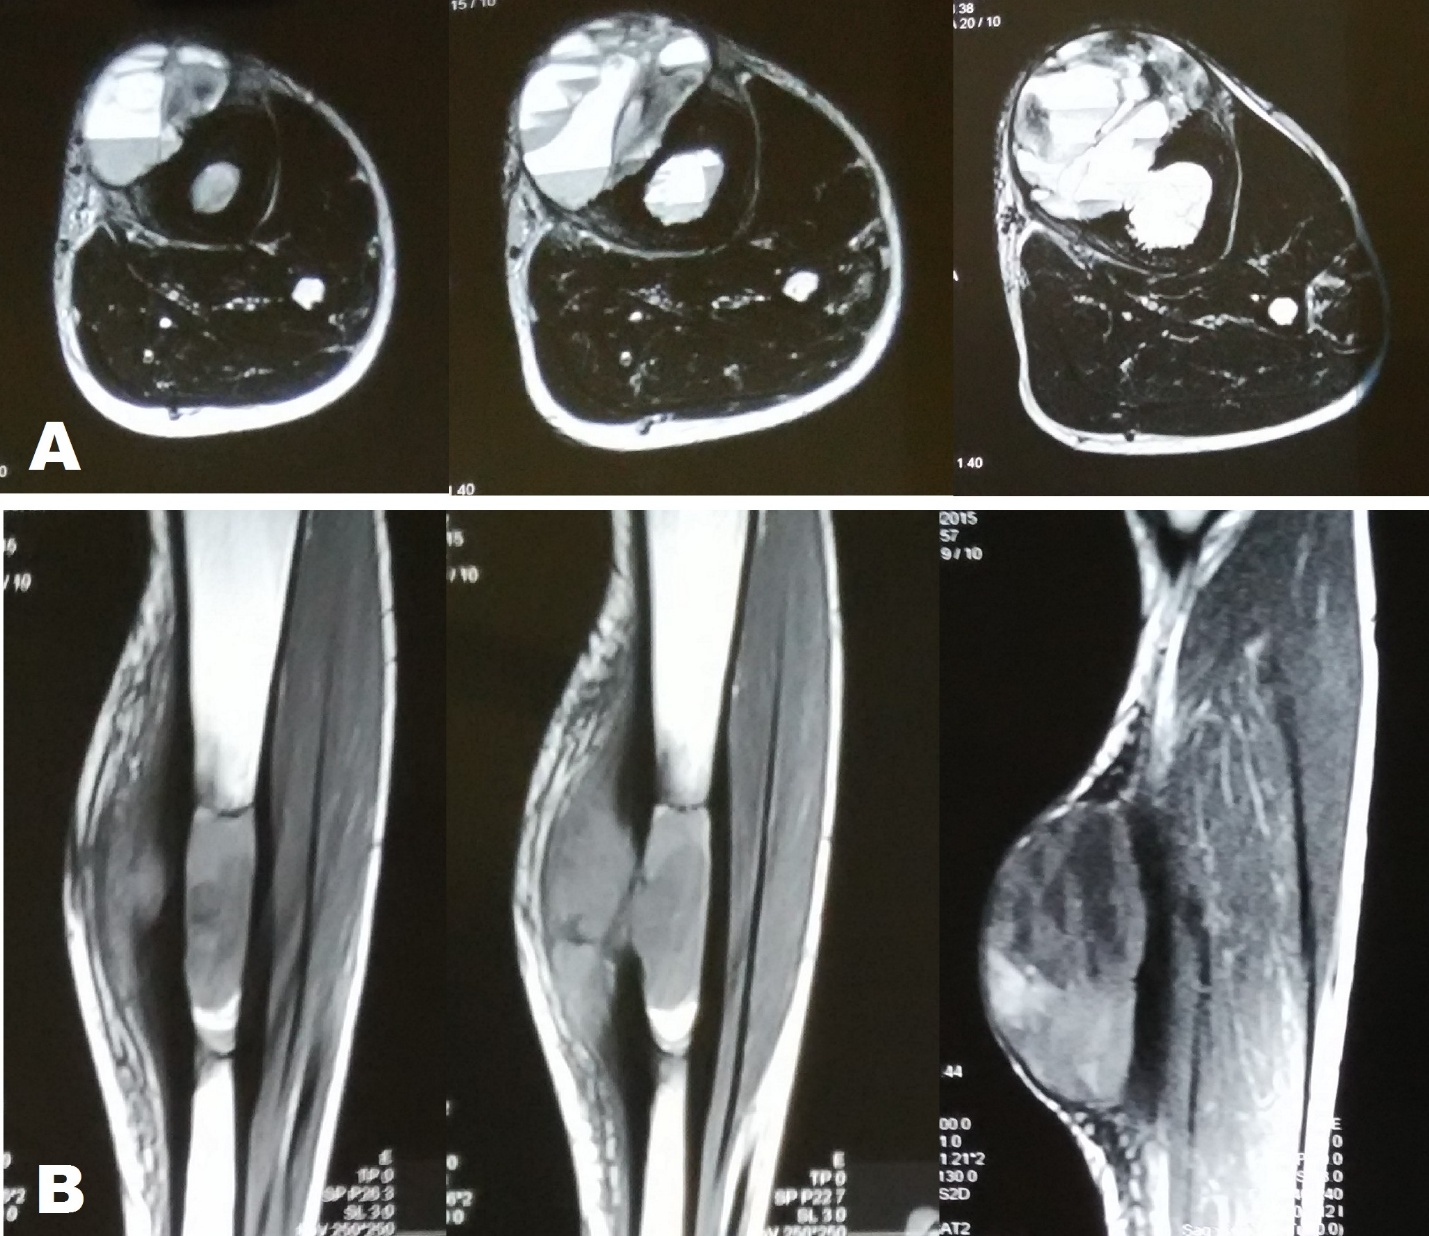

A 17 year old male patient from a remote area presented to our department with an eight month old history of trauma left shin after being hit by a cricket ball. Besides local pain patient developed a swelling over the middle of the shin after the traumatic episode which subsided in two weeks. The patient had not sought any medical consultation for the same. Five months after the trauma, patient felt mild dull pain and also noticed a swelling at the site of previous trauma which slowly progressed over three months before the patient reported to our hospital. On examination there was an oblong swelling measuring 17 cm in length and 12 cm in Figure 1 A). The swelling was immobile; its surface was smooth and was tender on deep palpation. The margins of the swelling were continuous with that of the tibia. On general physical examination there was nothing significant. Radiographic examination of the leg revealed an elliptical shaped lytic lesion along the antero-medial aspect of middle of tibial diaphysis. The lesion had a surrounding thick sclerosis and there was thick lamellate periosteal reaction. Radiographs also demonstrated soft tissue swelling which had very delicate bony trabeculae suggestive of soft tissue extension of the lesion (Figure 1 B). MRI of the leg demonstrated a large (91 × 26 × 60 mm) sized multi-loculated cystic lesion in the soft tissue of the leg in its mid part along with involvement of marrow of tibial shaft for approximately 65 mm in length. The lesion showed fluid-fluid levels in both intramedullary as well as the soft tissue components, giving an impression of aneurysmal bone cyst (Figure 2).